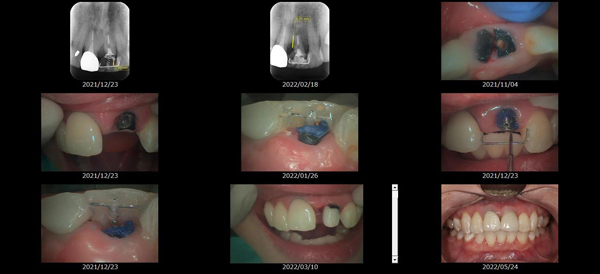

救歯MTM

虫歯が大きくて残せない歯、転倒などの事故により歯が根の深いとこで折れてしまったなどで、抜かざるを得ない歯を、骨の中に埋まっている健全な根を、骨の上に矯正的に引き上げることで、その歯を抜かず温存、救歯できる可能性のある治療方法です。

この特別な診療である救歯MTMは、以下のような特徴があります。

①健全な歯を、歯肉から見える位置にまで引き上げることで

根の治療の成功率を上げることが出来る。唾液には沢山の細菌がいます。唾液が入らない環境での根の治療を(神経の治療)を行うことで神経の治療、根の治療の成功率は格段と上がります。

②骨の上にある歯と土台で支える被せもの製作できる。

被せものを土台だけに頼ることなく、引き上げた健全な歯でも支えることで、歯への被せ物がしっかりと装着できるようになる。

③抜かずに歯を活かすことで、隣の歯を削るブリッジやインプラントにしないで済むことがある。

歯を矯正的に引き上げることで、その歯を救歯できるだけでなく、隣の歯を削るなどの侵襲を回避できる場合がある。

救歯治療と審美性の両立

当院では様々な治療の基礎に審美と機能の両立というテーマがあります。

リスク

- > 歯を矯正的に引き上げることで、骨の中の根の長さは短くなりますが、その短さでも安定するという診断をした場合のみ施術になります。 残せる歯、根の長さが短い場合は、この救歯MTMの治療対象とならない場合がございます。

- > 治療期間が数か月~1年に及ぶ場合がある。

- > 費用が自費診療 44,000円 ~ 66,000円

- > 救歯MTMは救歯BTAセラミックと併用治療が必要な場合があります。

症例